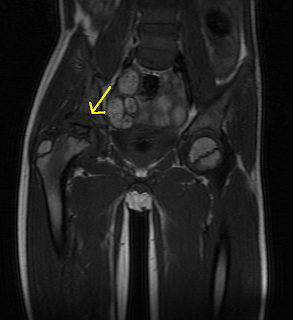

A study of 610 children under 12 years of age at disease onset. Legg calvé perthes disease is a condition characterized by a temporary loss of blood supply to the top of the femur. During healing, the socket part of the joint can serve as a mold to help the fragmented femoral head retain its round shape. This may mean careful explanation of the procedure and even immobilizing a child to decrease movement. It is more common in boys than in girls. Assessing the extent of cartilaginous involvement. A bone scan or mri may be useful if the diagnosis is. Note that the femoral head is completely contained inside the hip cup. Nord guide to rare disorders. Physical measurements of the thigh muscles and exams to assess the kids' range of motion are also performed as part of diagnosis. Perthes disease (lcpd) are based on subjective measures. A more detailed differentiation of waldenström's classification, especially in early and late fragmentation stages. Perthes disease is a rare kind of disability, primarily affecting the hip joint of children.

Rampal v, clément jl, solla f. Assessing the extent of cartilaginous involvement. Physical measurements of the thigh muscles and exams to assess the kids' range of motion are also performed as part of diagnosis. A study of 610 children under 12 years of age at disease onset. Perthes disease (lcpd) are based on subjective measures. A more detailed differentiation of waldenström's classification, especially in early and late fragmentation stages. Perthes' disease usually affects children between the ages of three and eleven years. Your doctor may request a bone scan, ultrasound or mri scan.

Your doctor may request a bone scan, ultrasound or mri scan. Impaired blood supply to the femoral head causes bone infarction. During healing, the socket part of the joint can serve as a mold to help the fragmented femoral head retain its round shape. Note that the femoral head is completely contained inside the hip cup. A bone scan or mri may be useful if the diagnosis is.

The aim of surgical intervention is to cover the femoral head as completely. Perthes disease (lcpd) are based on subjective measures. A bone scan or mri may be useful if the diagnosis is. Physical measurements of the thigh muscles and exams to assess the kids' range of motion are also performed as part of diagnosis. Rampal v, clément jl, solla f. Legg calve perthes disease sometimes called perthes disease or coxa plana, or avascular necrosis of the hip, is a bone disorder that affects the hips of children. Assessing the extent of cartilaginous involvement. During healing, the socket part of the joint can serve as a mold to help the fragmented femoral head retain its round shape.